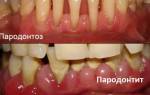

Важно отметить, что пародонтоз и пародонтит — это разные заболевания, хотя они поражают один и тот же тип ткани. У них разные причины возникновения, различные пути развития и требуют применения разных методов лечения. Кроме того, пародонтоз встречается редко, примерно у 3% пациентов.

Для отличия пародонтоза от пародонтита существует несколько признаков. Во-первых, пародонтоз является редким заболеванием, в то время как пародонтит распространен. Во-вторых, причиной пародонтоза является нарушение клеточного питания, в то время как пародонтит связан с плохой микрофлорой ротовой полости и наличием зубных отложений. В-третьих, пародонтоз затрагивает альвеолярные отростки всей полости рта, тогда как пародонтит может быть локализованным или распространяться на несколько десен. В-четвертых, при пародонтозе отсутствует воспаление десен, а главным процессом является атрофия, в то время как при пародонтите преобладает воспаление. В-пятых, пародонтоз не сопровождается абсцессами, гнойными выделениями, кровотечениями и патологическими зубодесневыми карманами, в отличие от пародонтита. И, наконец, при пародонтозе зубы начинают расшатываться постепенно, с течением времени, в то время как при пародонтите расшатывание зубов происходит уже на ранних стадиях заболевания.